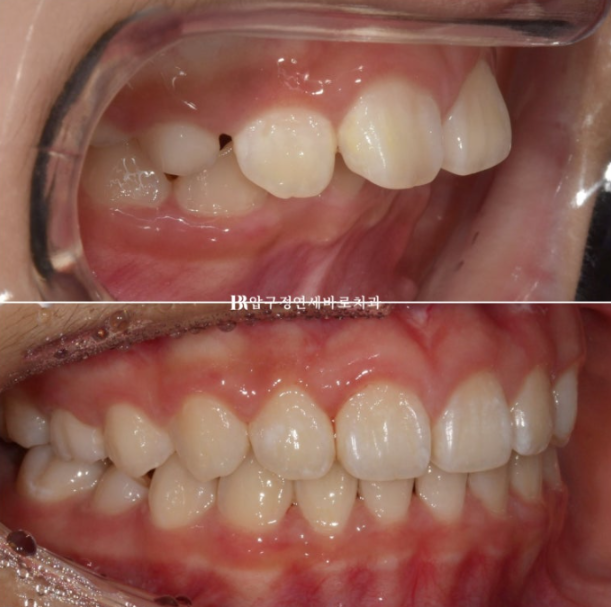

보증기간이 끝나기 직전에 17개월 차 쯔음 재제작을 한 번 더 하여 약간 돌아가있는 송곳니까지 완전히 배열을 마친 후 24년 8월에 드디어 치료를 종료했습니다.

24.09

22.08~24.09

돌출된 앞니 개선

처음에는 어린이였으나 2년 사이 어엿한 청소년이 되었습니다.

앞니 각도 스마일라인 모두 좋습니다.

앞니 돌출이 개선이 되면 입이 비로소 편하게 다물어집니다.

이정도 결과가 나오면 성인이 되어서도 굳이 교정을 안해도 됩니다.

좋은 결과 유지를 위해서 잘 때만 끼는 유지장치는 꼭 껴야하고 유지기간 저기체크 역시 잘 와야겠죠.